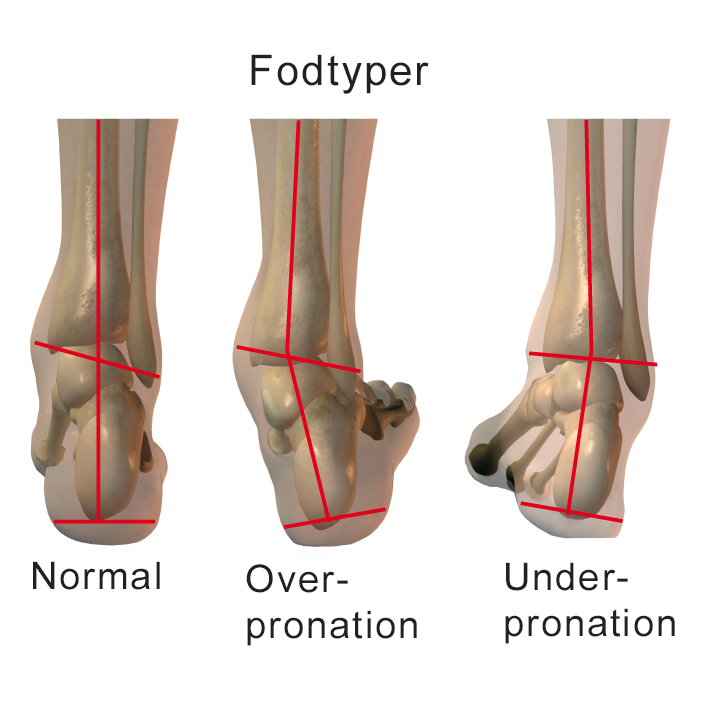

- Overpronation (indadtrådte fødder)

- Underpronation (udadtrådte fødder)

Fodens afvikling i forbindelse med løb foregår ved, at du stort set altid lander på ydersiden af hælen. Herefter ruller du hen over mellemfoden og afslutter ud over 1. og 2. tåen. Den måde, foden afvikler rullet på, kaldes pronation. Det er en af kroppens naturlige støddæmpningssystemer.

De tre mest almindelige fodtyper er normal fod, platfod og hulfod. De har hver især betydning for din løbestil og dermed for valg af løbesko.

Når foden er sat i underlaget under løb, vil den normale fod herefter oftest rulle lidt indad (pronere) for at absorbere stødet.

Hvis du har en flad fodtype og sætter foden i underlaget, vil den efterfølgende indadrullende fodbevægelse (pronation) ofte være overdrevet. Dette kaldes overpronation og medfører, at underbenet drejes mere indad end normalt ved løb. Hvis du ikke benytter en såkaldt pronationshæmmende løbesko, er der stor risiko for at få en overbelastningsskade.

Har man en hulfod er pronationen utilstrækkelig, når foden sættes i underlaget under løb, og støddæmpningen er ikke effektiv nok. Derfor kan der opstå overbelastningsskader. De bedste sko til denne fodtype er erfaringsmæssigt meget støddæmpende sko med masser af fleksibilitet i sålen.

Graden af under- eller overpronation kan bedst bedømmes ved videooptagelser af fodisæt under løb. Et anvendeligt mål for pronationen er at måle hælbenets vinkel med achillessenen i stående stilling med 45° fleksion i knæene. Er vinklingen i den stilling mere end 5 grader, kaldes det overpronation. Hvis der ikke kan fremkaldes en vinkling af hælbenet, og fodbuen er stiv selv ved drejebevægelser, kaldes det underpronation. Derudover kan fodtøjet i reglen afsløre underpronation og overpronation ved vinkling af hælkappen og øget slitage af hhv. ydersiden eller indersiden af sålen.